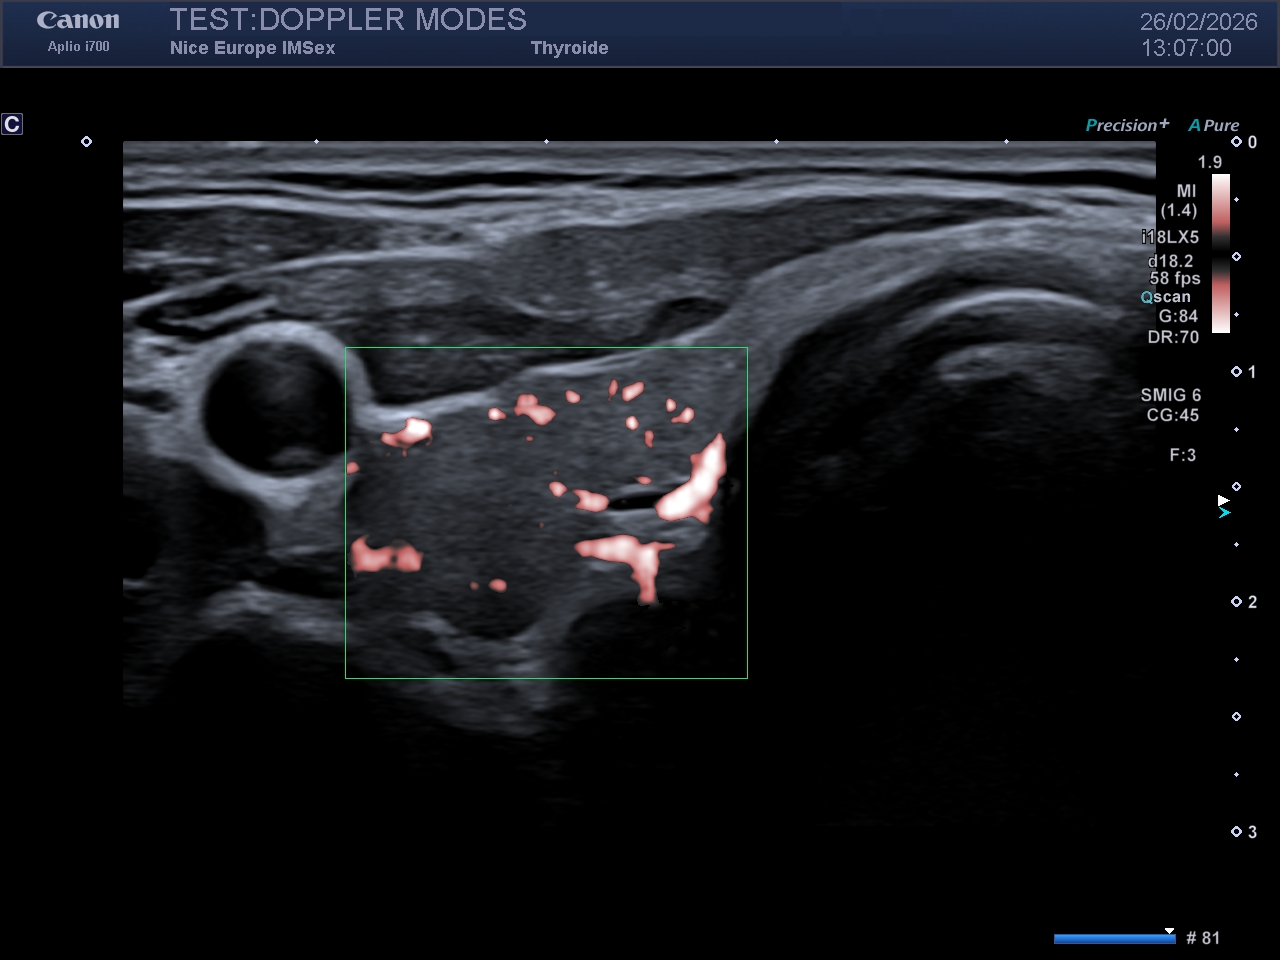

Les modes microvasculaires de dernière génération (déclinés selon les constructeurs sous diverses appellations telles que SMI - Superb Micro-vascular Imaging, MFI - MicroFlow Imaging, MV-Flow, Micro Angio, LumiFlow, etc.) contournent ce problème grâce à l'imagerie ultrarapide. Au lieu d'émettre des faisceaux focalisés ligne par ligne, la sonde émet des "ondes planes" non focalisées balayant l'ensemble de la zone en une seule émission. Cette technique permet d'acquérir des milliers d'images par seconde.

Cette résolution temporelle extrême permet d'abandonner le filtrage fréquentiel classique au profit d'un filtrage spatio-temporel avancé, basé sur la Décomposition en Valeurs Singulières (SVD). La SVD sépare les signaux selon leur cohérence spatiale et temporelle : le mouvement des tissus (cohérent) est mathématiquement dissocié du mouvement des hématies dans les capillaires (incohérent).

Impact Clinique :

Le résultat est une cartographie microvasculaire d'une résolution spatiale inouïe, limitant drastiquement les artefacts de débordement (blooming artifact). Ce mode excelle dans la caractérisation fine de l'angiogenèse tumorale ou l'évaluation de l'activité inflammatoire tissulaire.